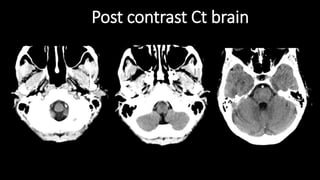

Post contrast Ct brain